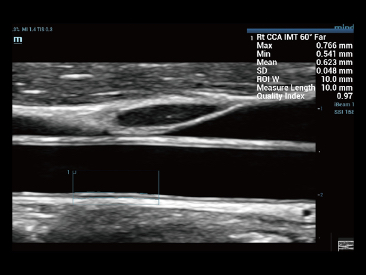

Since the company was founded, Mindray has been continuously exploring new ways to improve diagnostic confidence. Powered by the most revolutionary ZONE Sonography? Technology, Resona 7ŌĆÖs new ZST+ platform brings ultrasound image quality to a higher level by zone acquisition and channel data processing.

As well as the premium level image quality, Resona 7 also enhances clinical research capabilities with the revolutionary V Flow for vascular hemodynamic evaluation, and the most intelligent plane acquisition from 3D datasets for fetal CNS diagnosis. Combining the most intuitive gesture-based multi-touch operation and all the essential clinical features, Resona 7 is truly leading new waves in ultrasound innovation.